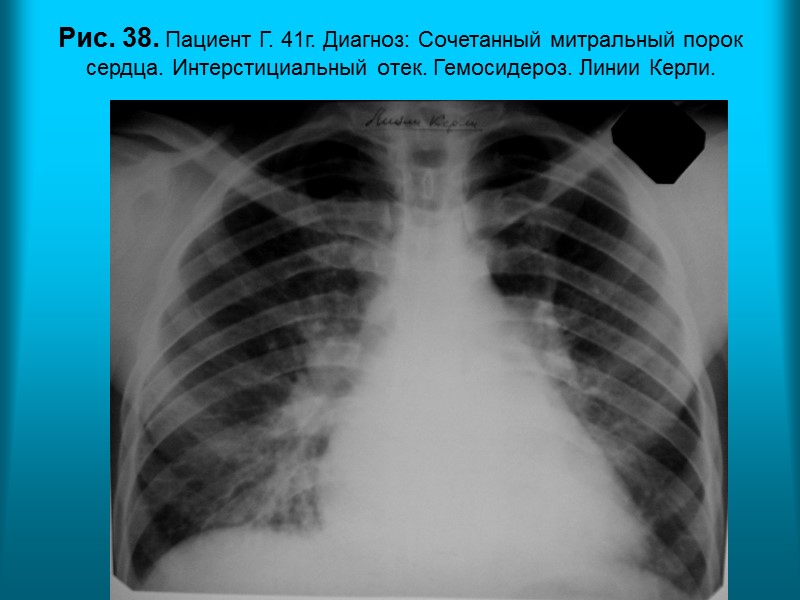

Н.С. Воротынцева. С.С. Гольев Рентгенопульмонология Рис. 38. Пациент Г. 41г. Диагноз: Сочетанный митральный порок сердца. Интерстициальный отек. Гемосидероз. Линии Керли.